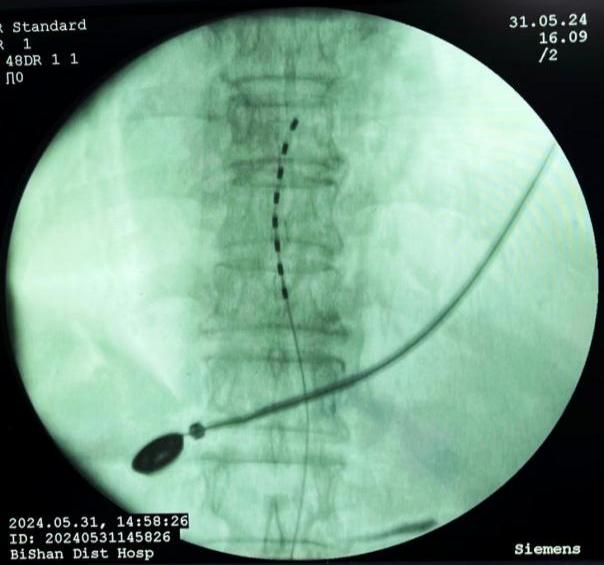

膠原酶椎間盤化學(xué)溶解術(shù),是在影像引導(dǎo)下(C型臂X線機(jī)或CT),將膠原酶準(zhǔn)確地注射到突出的椎間盤內(nèi)及其周圍,使突出的椎間盤溶解并吸收,解除其對神經(jīng)根的壓迫,進(jìn)而緩解癥狀。

椎間盤射頻消融術(shù)、膠原酶椎間盤化學(xué)消融術(shù)